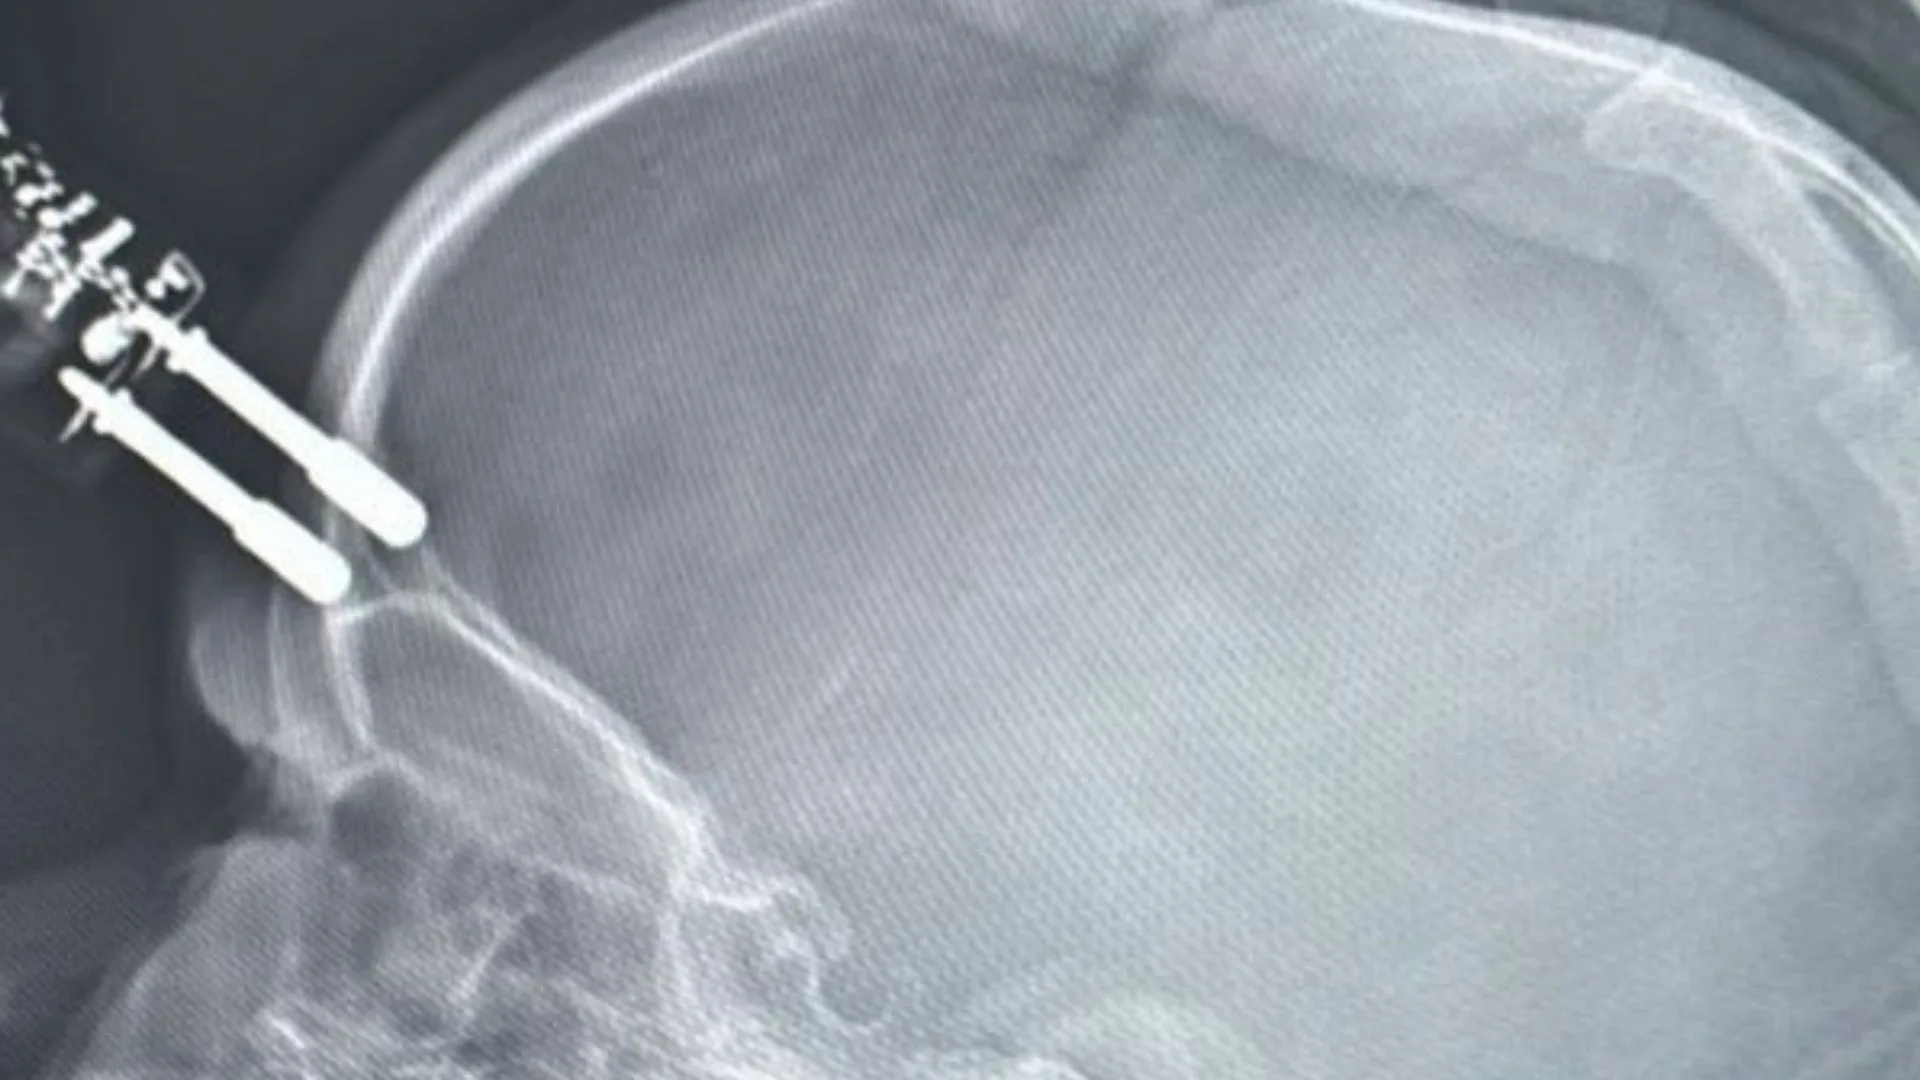

Uma menina de 1 ano e quatro meses sofreu um grave acidente doméstico ao cair da cama e ter a testa perfurada por um carregador de celular que estava no chão. O acidente aconteceu na noite de segunda-feira (12), em Divinópolis, na região oeste de Minas Gerais. Segundo o neurologista Bruno Castro, o carregador chegou a perfurar o crânio da criança, causando uma fratura.

A menina foi atendida primeiro na Unidade de Pronto Atendimento (UPA) de Divinópolis e, em seguida, transferida para o Hospital São João de Deus. Lá, passou por cirurgia de emergência para retirada do carregador, correção da lesão e contenção de um pequeno sangramento.

Após a operação, a criança ficou 36 horas no Centro de Terapia Intensiva (CTI), passou por tomografia de controle e apresentou boa evolução clínica. Por se tratar de um objeto contaminado, permaneceu internada recebendo antibióticos, mas, segundo os médicos, está se recuperando bem e deve receber alta em breve.